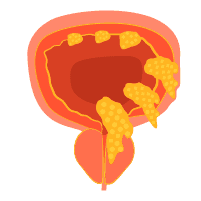

Bladder Cancer (ဆီးအိမ်ကင်ဆာ)

အဓိပ္ပါယ်ဖွင့်ဆိုချက်Bladder Cancer (ဆီးအိမ်ကင်ဆာ) ကဘာလဲ။ ဆီးအိမ်ကင်ဆာဆိုသည်မှာဆီးများကိုသိုလှောင်သောတင်ပဆုံနေရာရှိ ပူဖေါင်းပုံဆီးအိမ် တွင် ဖြစ်ပွားသောကင်ဆာတစ်မျိုး ဖြစ်ပါသည်။ ဆီးအိမ်ကင်ဆာသည် ဆီးအိမ်အတွင်းနံရံကိုကာထားသောဆဲလ်များတွင် စတင်ဖြစ်ပွားလေ့ရှိပါသည်။ ဆီးအိမ်ကင်ဆာအများစုသည် ကုသ၍လွယ်သောအစောပိုင်းအဆင့်တွင် ရောဂါ အဖြေရှာသိရှိနိုင်ပါသည်။ သို့သော် အစောပိုင်းအဆင့်ဆီးအိမ် ကင်ဆာသည်လည်းထပ်မံဖြစ်ပွားနိုင်ပါသည်။ ထို့ကြောင့် ဆီးအိမ် ကင်ဆာပျောက်ကင်းသူမျာသည် နောက်ဆက်တွဲ စစ်ဆေးမှုများကိုရောဂါပျောက်ပြီး နှစ်အနည်းငယ် ကြာသည် အထိ ပြုလုပ်ရန် လိုအပ်ပါသည်။ Bladder Cancer (ဆီးအိမ်ကင်ဆာ) က ဘယ်လောက်အဖြစ်များသလဲ ဆီးအိမ်ကင်ဆာသည် မည်သည့်အသက်အရွယ်တွင်မဆို ဖြစ်ပွားနိုင်သော်လည်းအသက်ကြီးသောလူများတွင် ပိုဖြစ်ပွားတတ်ပါသည်။ အမျိုးသားကျန်းမာရေးအဖွဲ့အစည်းအရတစ်နှစ်တွင် အမျိုးသား ၄၅၀၀၀ နှင့် အမျိုးသမီး ၁၇၀၀၀ သည် ဤရောဂါ ဖြစ်ပွားပါသည်။ သို့သော်လည်း အန္တရာယ် ရှိသောအချက်များကိုလျော့ချခြင်းအားဖြင့် ရောဂါကိုထိန်းချုပ် နိုင်ပါသည်။ ပိုမိုသောအချက် အလက် များအတွက် ဆရာဝန်နှင့် တိုင်ပင်ပါ။ လက္ခဏာများBladder Cancer (ဆီးအိမ်ကင်ဆာ) ရဲ့လက္ခဏာတွေကဘာတွေလဲ ဆီးအိမ်ကင်ဆာဝေဒနာသည်များသည် […]